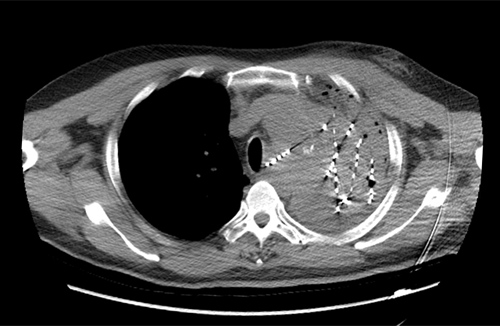

56岁的贵先生确诊左肺鳞癌两年半,两年来先后在多家医院给予放射治疗、多周期化疗、抗血管生成药物及靶向药物治疗等。近期病情再次加重,多次出现大咯血等情况,患者及家属一度绝望,后辗转到临床医学院/附属医院。呼吸内一科医生根据患者病情进行多次讨论,决定在咯血稳定后,为患者实施肿瘤内碘125I粒子植入术。此次手术为该院首例CT引导下肺癌放射性粒子植入术,过程顺利,术后CT显示粒子分布良好,经后续监护及观察,患者无特殊不适,原有胸痛胸闷症状明显缓解,达到治疗预期效果。据悉,碘125I粒子植入术作为组织间近距离放疗的一种新手段,自被证实为治疗肺癌安全有效、无严重副作用的治疗手段以来,国际国内正逐步开展,打开了肿瘤微创治疗的新篇章,临床医学院/附属医院呼吸一科紧跟学科发展,积极引进,为癌症患者带来了福音。